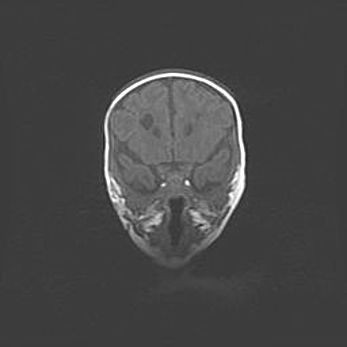

Сообщающаяся гидроцефалия. Кистозная энцефаломаляция головного мозга.

Возраст: 3 месяца 4 дня

Вес: 3100 г

Пол: женский

Окружность головы: 34 см

Срок гестации: 31 неделя

Кистозная энцефаломаляция головного мозга - одна из форм поражения головного мозга в детском возрасте. Характеризуется возникновением множественных и распространённых кист в коре, белом веществе и подкорковых образованиях головного мозга у плодов, новорождённых и детей раннего возраста. Развитие кистозной энцефаломаляции связано с внутриутробной асфиксией и гипотонией, родовой травмой, тромбозом синусов, пороками развития сосудов, инфекциями, сепсисом и другими причинами. Наиболее значимые инфекционные агенты: вирусы простого герпеса, цитомегалии, краснухи, токсоплазмы, энтеробактерии, золотистый стафилококк и другие.